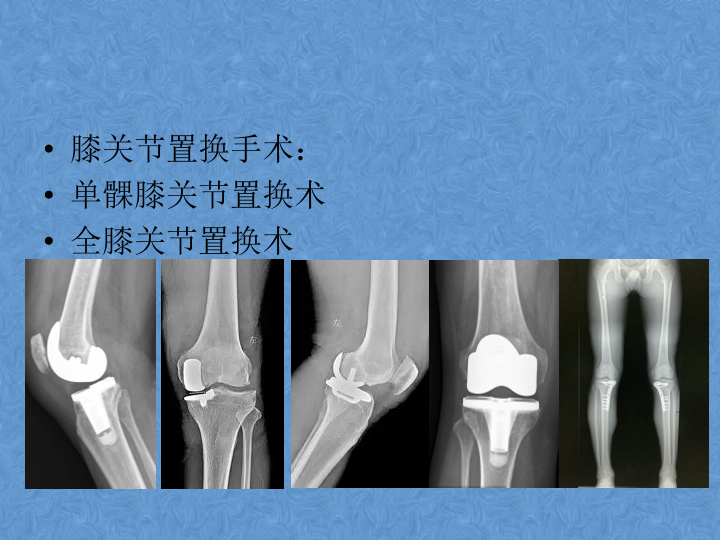

骨关节炎的阶梯治疗